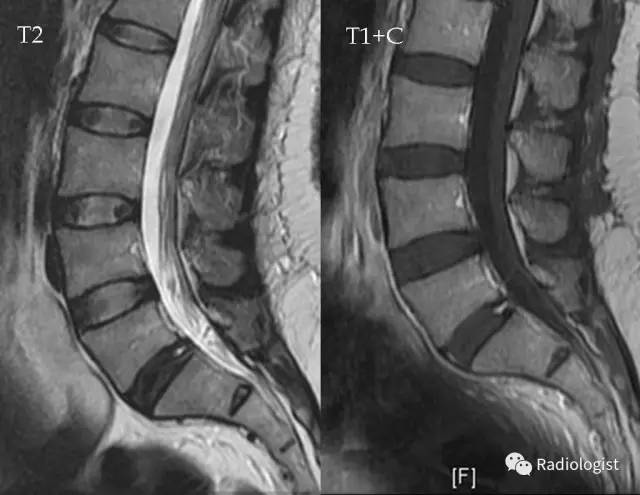

纤维环裂隙annularfissures

腰椎纤维环撕裂